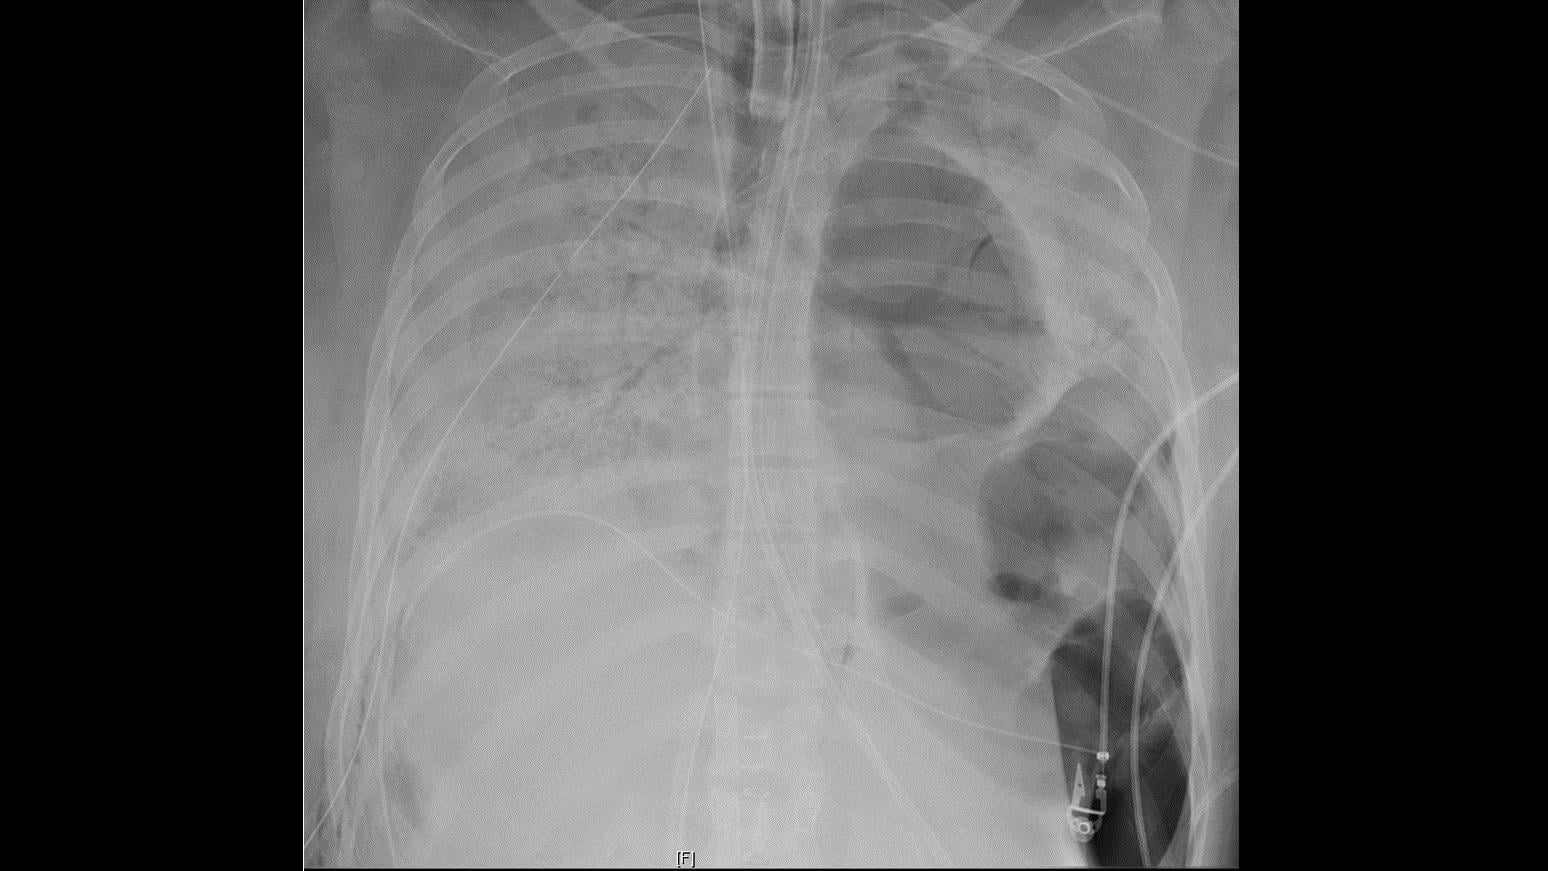

Covid 19 and Lung Transplant Patients

These are the latest Covid 19 and Lung Transplant Patients images from around the world.